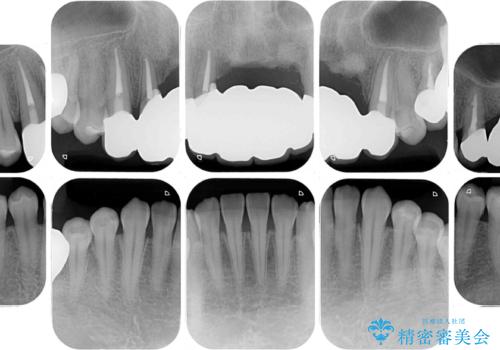

- ソーシャルメディアでのゲームに夢中になっている最中に車と接触し、前歯の抜歯を余儀なくされた患者様です。

初診時では前歯が保存できる可能性も模索しましたが、損傷が激しく3歯を抜去することとなりました。

保存となった隣在歯も神経が失活していており、補綴治療が必要であったので、オールセラミッククラウンにて補綴治療することとしました。

奥歯には元々欠損があり、欠損に伴う咬合不正も認められたため、部分矯正を行った上でインプラント補綴治療も行うこととしました。